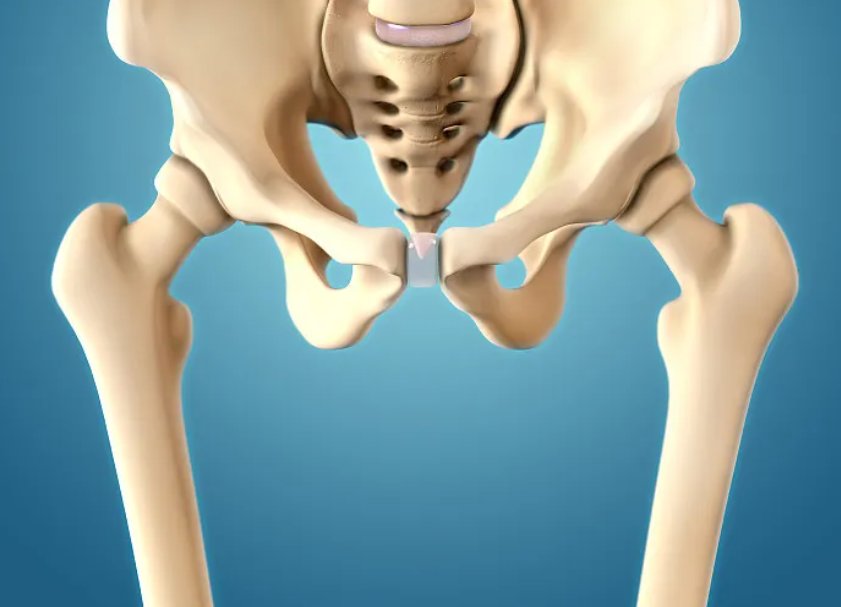

五、人体大腿骨硬度超乎想象,1立方厘米可承载5辆越野车重量

人体骨骼的坚硬程度,往往被我们低估,尤其是大腿部位的股骨,堪称人体最坚硬、承重能力最强的骨骼。很多人误以为骨骼很脆弱,稍微受力就会骨折,实际上成年人的股骨,是由钙、磷等矿物质和胶原蛋白紧密结合构成,结构致密、韧性与硬度兼具,既能承受冲击力,又有极强的抗压能力。

根据生物力学实验数据显示,将人体股骨的骨密质部分,压缩至1立方厘米的体积,它的抗压强度可以达到1500-2000兆帕,足以承载5辆大型越野汽车的总重量。股骨作为人体下肢的核心承重骨骼,日常支撑着人体的全部体重,跑步、跳跃、负重时,能承受数倍于体重的压力,正是因为它超强的硬度和承重能力,才能保障我们正常的下肢活动。

不过随着年龄增长、钙质流失,中老年人的股骨会出现骨质疏松,骨密度下降、脆性增加,骨折风险大幅提升,所以日常补充钙质、维生素D,适度运动锻炼,保护股骨和骨骼健康,对维持身体活动能力至关重要。